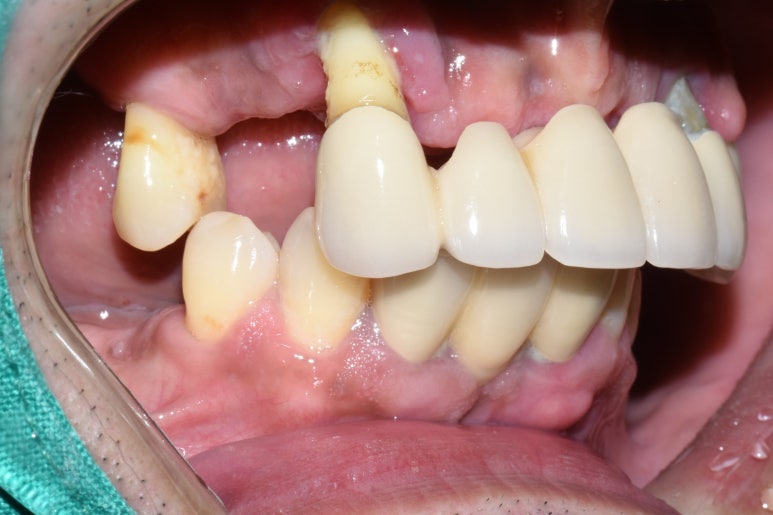

처음 오셨을 때 치아 사진입니다.

앞니가 너무 많이 흔들리고 남은 작은 어금니도 상태가 좋지 않아 다 뽑고 전체틀니를 하기로 했다가

환자분이 아직 50대이시기도 하고 뺐다꼈다 하는 틀니보다는

장기적으로 생각했을 때 임플란트를 하는게 낫다고 판단하신데다가

저희 치과가 서울에서 유명한 임플란트 전문이라고 주변에서 얘기를 들으셨다며

상악 전체임플란트를 하기로 하셨습니다.